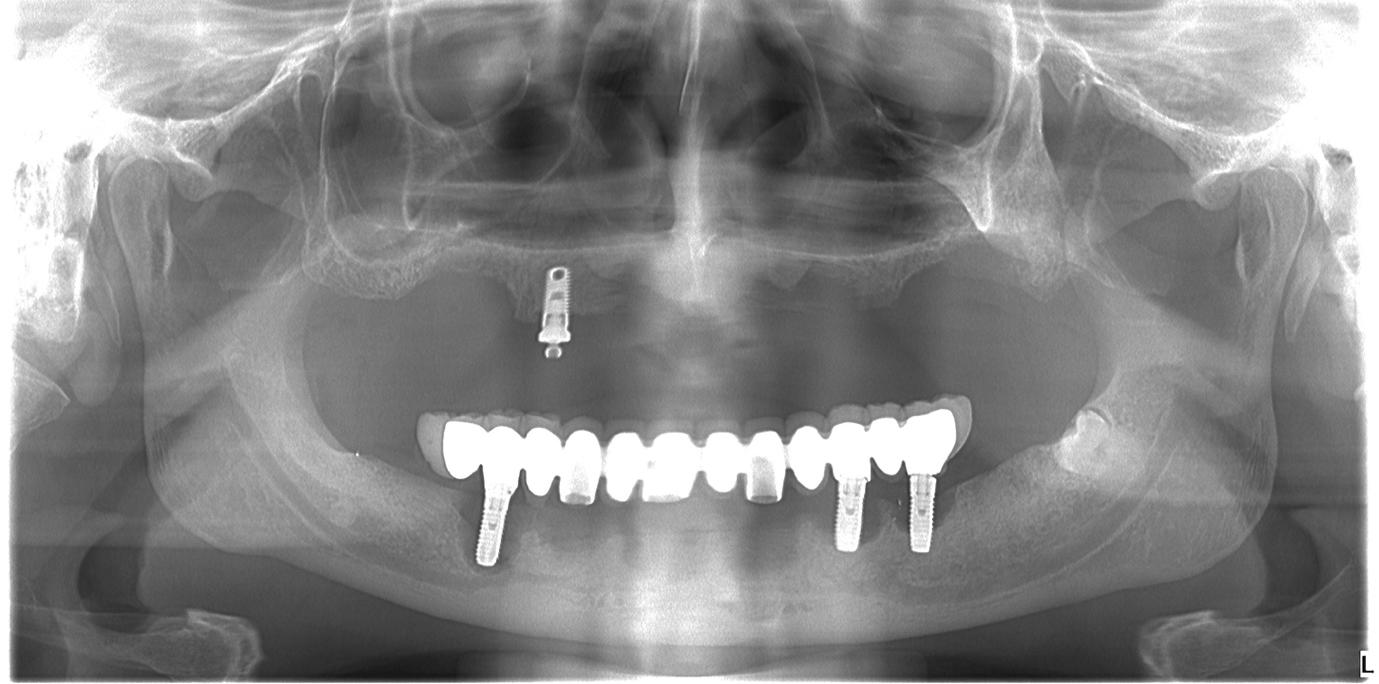

20–22. ábra: 2017-es, 2019-es és 2022-es panorámaröntgen-felvételek.

A műtétet követően napi kétszeri, 0,12%-os klórhexidin tartalmú szájvízzel történő öblögetést javasoltunk a páciensnek, két héten keresztül. Gyulladáscsökkentésre 8 óránként 400 mg Ibuprofént javasoltunk, három napon keresztül. A páciens elmondása szerint sem fájdalmat, sem különösebb diszkomfortot nem tapasztalt. Ezt követően, további 4 héten keresztül, 0,2%-os klórhexidin tartalmú szájvízzel történő öblögetést javasoltunk a betegnek és instruáltuk, hogy lehetőleg ne mossa fogkefével az érintett területet. A varratokat egy héttel később távolítottuk el. A donor és a recipiens terület – 10 nappal a műtétet követően – kiválóan gyógyult (15–16. ábra). Az ezt követő kontrollokat a következő időpontokban ejtettük meg: kettő, illetve négy héttel a műtét után, majd három, hat és tizenkét hónappal később, ezt követően pedig félévente (17–20. ábra). Minden kontroll alkalmával professzionális fenntartó kezelést végeztünk a területen.

15. ábra: Tíz nappal a műtét után készült kép, kiválóan gyógyult mind a donor, mind a recipiens terület.

ságát egy ISO #15-ös endodonciai fájllal mértük 2 mm-re a marginális ínyszéltől meziálisan, disztálisan, illetve az implantátum tengelyében (mint referenciapont). A keratinizált íny szélességét parodontológiai szondával regisztráltuk a kiindulás és a kontrollvizsgálatok alatt. A méréseket elvégeztük a műtét előtt, közvetlenül utána, 4 héttel később, majd egy és két év elteltével. A klinikai paramétereket (keratinizált íny szélessége, lágyszövet volumen és recessziófedés) regisztráltunk a kiinduláskor és az utánkövetés időpontjai alatt. Kiinduláskor a feszes íny szélessége minimális volt (1 mm). A keratinizált ínyszélesség terén négy hétnél 2 mm-t sikerült nyerni, egy évnél 3 mm-t és öt év alatt 5 mm-t. A recessziót 100%-osan sikerült fedni 4 hét után, és ez nem változott sem egy év, sem öt év után.